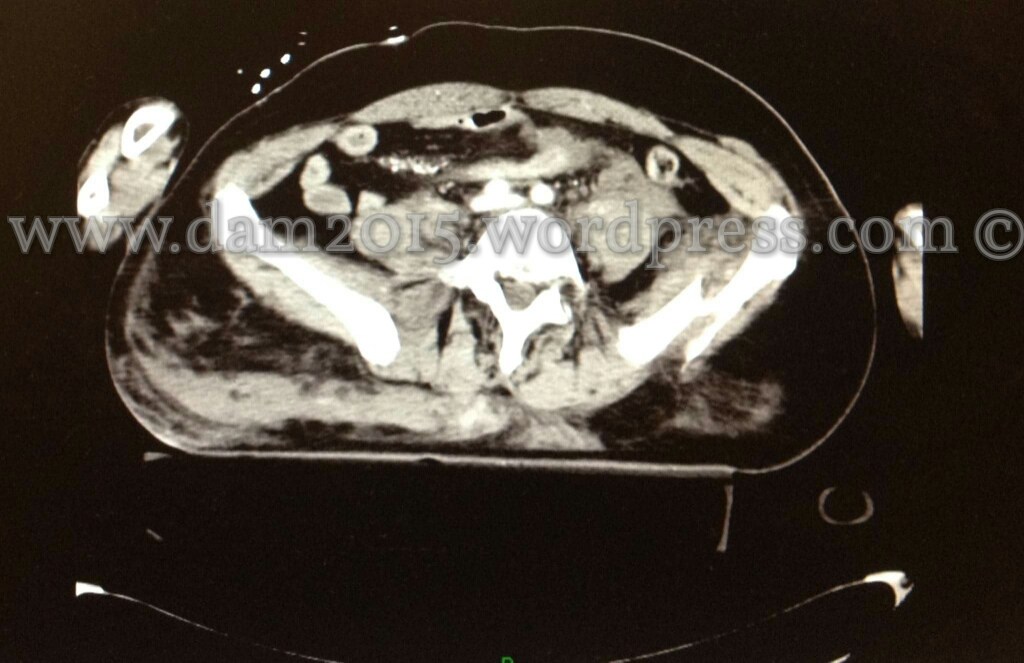

Pz donna, 56 anni.

Incidente stradale.

Shock emorragico in fratture multiple del bacino. Emoperitoneo.